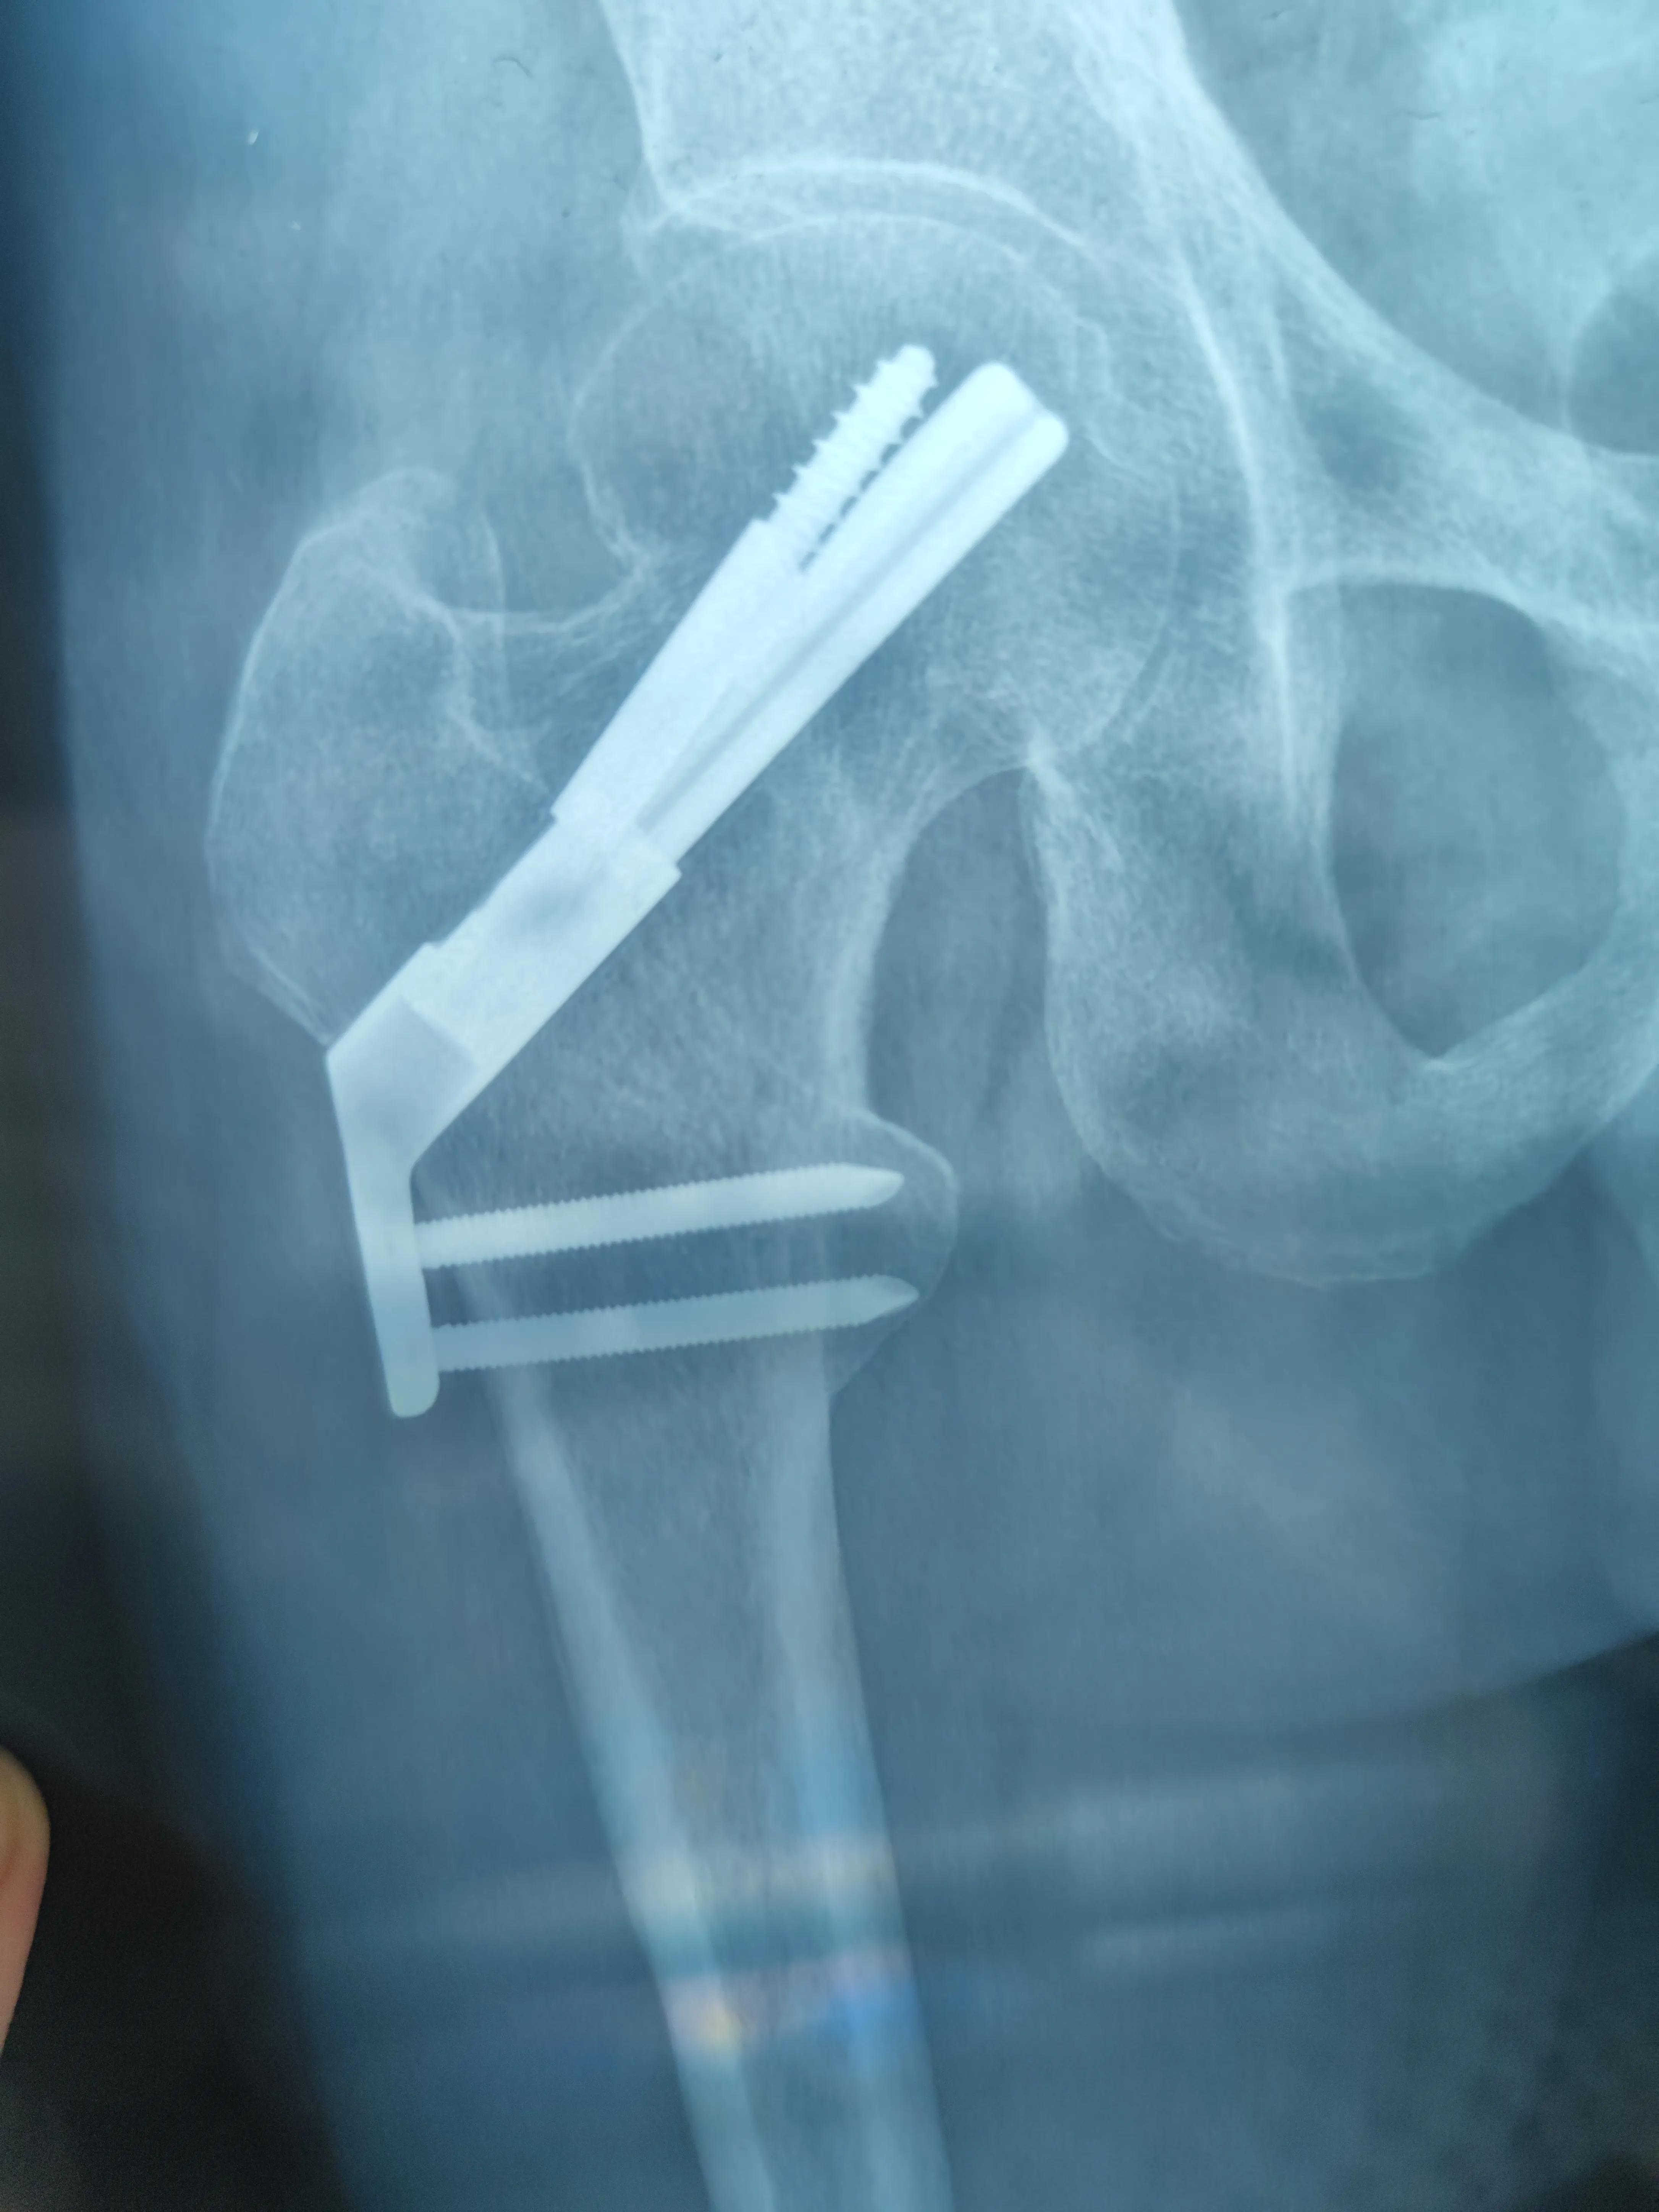

然后的然后,当时也不知道过了多久,慢慢的有了意识,有意识后首先发现自己被扒的一丝不挂,只是在*体下**位置盖一白色浴巾,两个护士小姐姐拿着热风管在我身体上来回的吹热风,然后我微微动了下伤腿,发现没有术前那么疼了,可能是麻醉还没过去原因。记得大概过了半小时左右,把我推出了手术室,送回了病房!然后主治医师进来了,拿着手术室的透视片给我说:手术很成功,骨折端复位很好,基本上都看不到骨缝了.我当时也没细看,再说也看不懂,就只说了声谢谢医生,辛苦了!然后简单的交代了一下,就走了,也没交代让我穿丁字鞋,夹枕头等等…大约又过了半小时左右,进来两名护士,给我拔掉了引流管与尿管!输上了液体,罩上了氧气,夹上了心电图…这个过程持续了一晚上…

图(3)术后x片